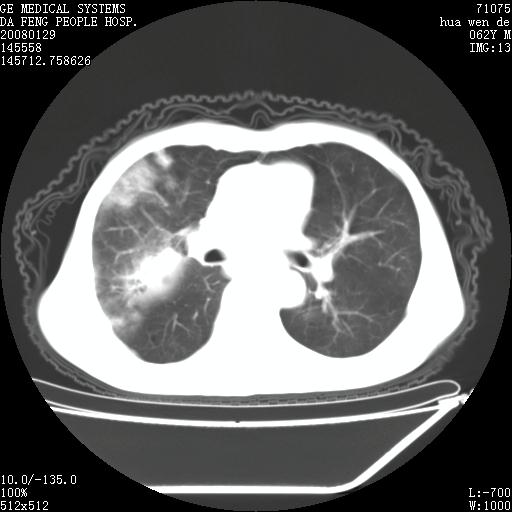

男性,67岁。作肺部检查时发现

1.整个食管扩张,未见明显占位性病变,贲门区亦未见明显占位病变,考虑:贲门失驰缓症;

2.右上肺病变边缘可见毛刺,囊壁厚度不均匀,周围境界较清楚,未见炎性渗出性影,右上肺外带可见片状影,边缘不清,考虑:肺癌伴空洞形成、右上肺炎。

食管全程扩张,壁均匀不厚,喷门失弛缓症

右上肺空洞可见液平,临近肺野磨玻璃密度,考虑1.结核2.脓肿

贲门失驰缓症.肺部感染伴脓肿形成。支持!是否吸入性要结合临床诊断,我们影像是看不出来的。但胸腔胃能排除(1.没有手术史支持,2.双侧胸廓对称,胸壁、肋骨及胸膜规整,3,食管壁明显扩张内壁光滑,胸腔胃黏膜皱襞多较厚)。

右上肺空洞可见液平,临近肺野磨玻璃密度,考虑1.结核2.脓肿 支持!